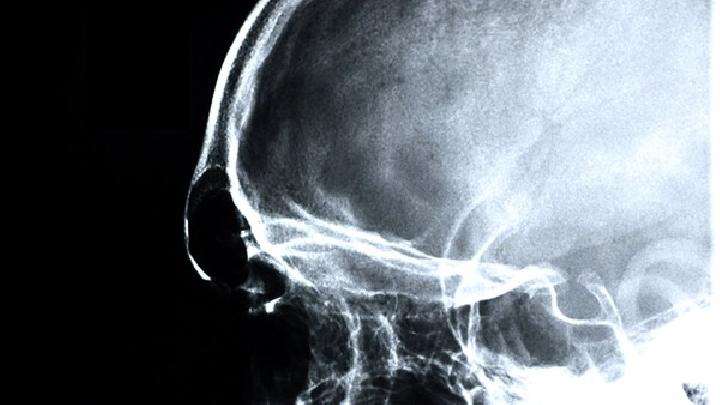

影像学检查

1.CT检查

临床疑诊脑出血时首选CT检查,可显示圆形或卵圆形均匀高密度血肿,边界清楚,并可确定血肿部位、大小、形态,以及是否破入脑室、血肿周围水肿带和占位效应等;如脑室大量积血可见高密度铸型,脑室扩张。l周后血肿周围可见环形增强,血肿吸收后变为低密度或囊性变。CT动态观察可发现进展型脑出血